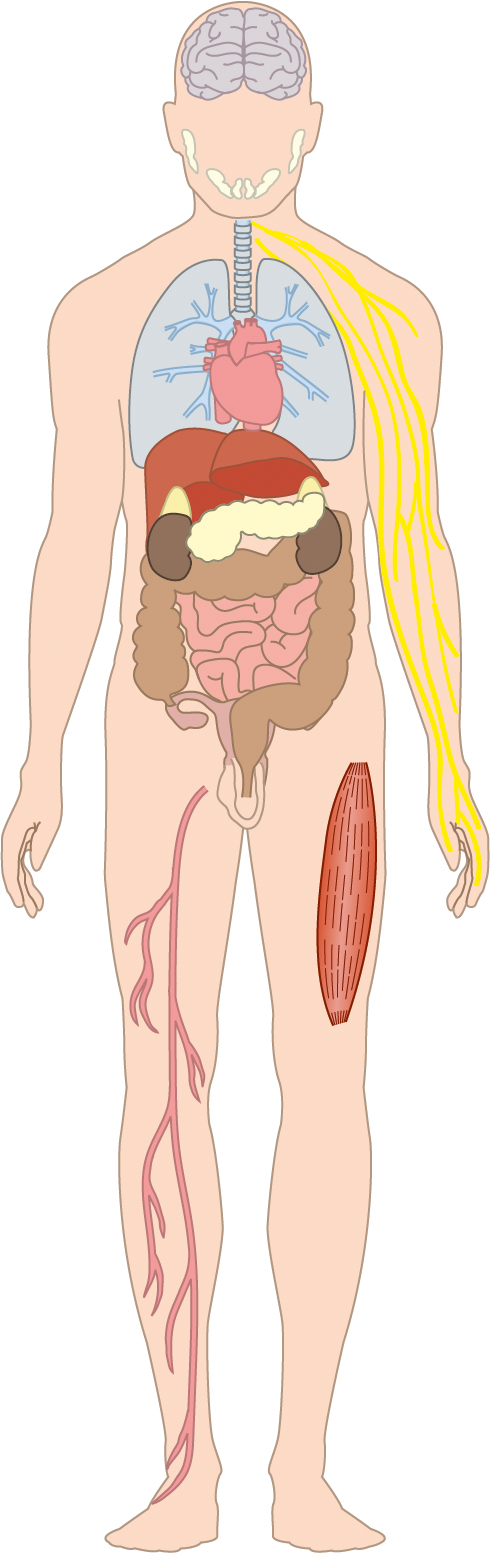

Herzlich willkommen! Ich bin Ihre Expertin für medizinische Illustrationen und kreative Kinderbuch-Illustrationen. Mit einem Auge für wissenschaftliche Genauigkeit und einer Liebe zur Gestaltung kindgerechter Erzählwelten schaffe ich Bilder, die informieren und begeistern. Entdecken Sie mein Portfolio und lassen Sie sich von meiner Arbeit überzeugen!